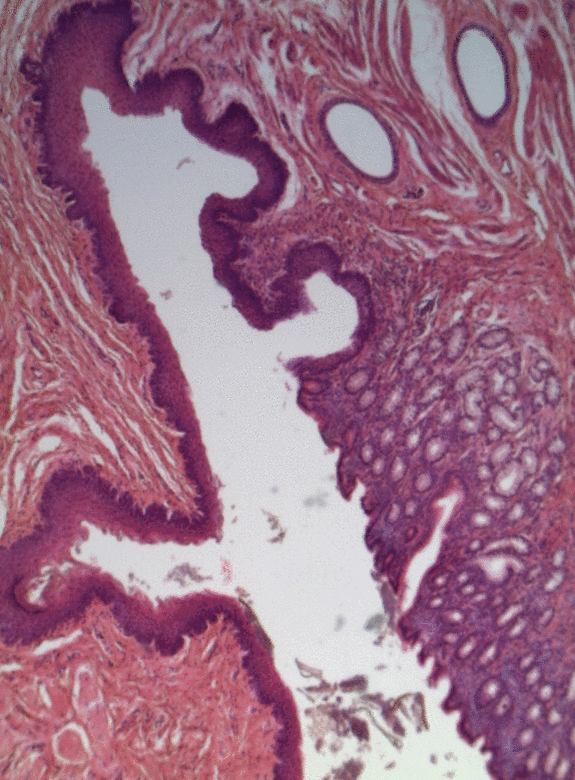

В многослойных эпителиях с базальной мембраной связаны только клетки самого нижнего (базального) слоя. В многослойном плоском неороговевающем эпителии различают три слоя: базальный, шиповатый (промежуточный) и плоский (поверхностный). Клетки базального слоя кубические или призматические, среди них имеются стволовые клетки, сохраняющие способность к митозу; именно благодаря делениям этих клеток популяция эпителиоцитов восстанавливается, несмотря на постоянное отмирание поверхностных клеток эпителия. Шиповатый слой образован эпителиоцитами неправильной многоугольной формы. Клетки базального и шиповатого слоёв содержат хорошо выраженные пучки тонофиламентов кератина. Плоские клетки, образующие поверхностный слой эпителия, постоянно отмирают и отпадают с поверхности эпителия, однако, в отличие от роговых чешуек многослойного плоского ороговевающего эпителия, в них различимы ядра. Многослойный плоский неороговевающий эпителий покрывает роговицу глаза, выстилает ротовую полость и пищевод[33], а также влагалище[17] и покрывает настоящие Голосовые связки[34]. Многослойный неороговевающий эпителий, содержащий множество одноклеточных слизистых желез, покрывает тело у круглоротых и хрящевых рыб[35].

Мочеотводящие органы (почечные лоханки, мочеточники, мочевой пузырь, уретра) выстланы особым переходным эпителием, который даёт возможность этим органам сильно растягиваться при заполнении мочой. Своё название он получил в связи с тем, что ранее считалось, что он является переходной формой между многослойным столбчатым и многослойным плоским эпителиями. Поскольку переходный эпителий встречается только в мочеотводящих путях, его также называют уротелием[42]. Переходный эпителий обычно достигает 4—6 клеток в толщину[43]. В переходном эпителии выделяют три слоя: базальный, промежуточный, поверхностный. Базальный слой образуют невысокие цилиндрические или кубические клетки[32]. Промежуточный слой образован клетками многоугольной формы. Клетки поверхностного слоя очень крупные, нередко содержат два или три ядра, и в зависимости от степени растяжения стенки органа и его заполненности мочой имеют куполообразную или уплощённую форму. Когда стенка органа сокращается, некоторые клетки промежуточного слоя выходят на границу с поверхностным слоем и принимают грушевидную форму, а расположенные над ними поверхностные клетки становятся куполообразными. Когда орган заполнен мочой, но его стенка не сокращается, эпителий становится более тонким, поверхностные клетки принимают уплощённую форму[44].